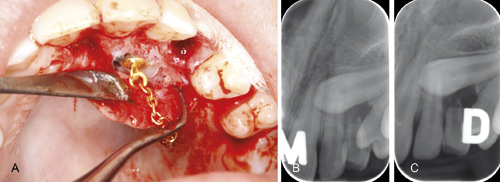

Pasienter med palatinalt retinert maxillære hjørnetenner som ikke bryter frem som normalt, vil ofte trenge en kombinasjon av kjeveortopedisk og kirurgisk behandling. Dette kan i mange tilfeller være teknisk vanskelig og tidkrevende for behandleren og kan gi peroperative og postoperative komplikasjoner for pasienten. I dag er det to kirurgiske metoder som benyttes, åpen fremføring uten feste av sleper eller lukket fremføring med feste av sleper. Hvilken metode som er mest fordelaktig har vært tema for diskusjon. Ved Det odontologiske fakultet i Oslo, Avdeling for oral kirurgi og oral medisin, UiO, er lukket fremføring med feste av sleper standard behandling når en hjørnetann er retinert både i palatinal og buccal posisjon. Målet er å oppnå festet gingiva rundt tannen etter frembrudd. Under inngrepet legges en lapp opp og overliggende ben fjernes slik at kronen eksponeres, eventuell blødning kontrolleres og tannen tørrlegges og klargjøres til feste av sleper. Deretter replasseres mucoperiostlappen og ved hjelp av ortodontisk apparatur vil tannen dras frem under lappen (Figur 1). Kjeveortopedisk bracket festes på tannen idet den er tilstrekkelig eksponert. Fremføring, korreksjon til riktig posisjon i tannbuen og retensjonsfase gjennomføres innen debonding finner sted (1, 6). Selv om fremføring med feste av sleper er en veletablert og tilfredsstillende metode, er det flere som kritiserer lukket fremføring i å være mer teknikksensitiv og mer tidkrevende enn åpen fremføring (7). Andre igjen mener at både palatinal og labial lapp i kombinasjon med en godt festet sleper gir forutsigbar erupsjon og få komplikasjoner (8).

Figur 1 A-C. En 14 år gammel gutt med palatinal retinert 23. A: Etter at man har lagt opp en mucoperiostal lapp og fjernet overliggende ben er en kjeveortopedisk bracket og lenke festet til palatinalsiden av 23. B, C: røntgenpeiling av 13 viser palatinal posisjon av tannen.